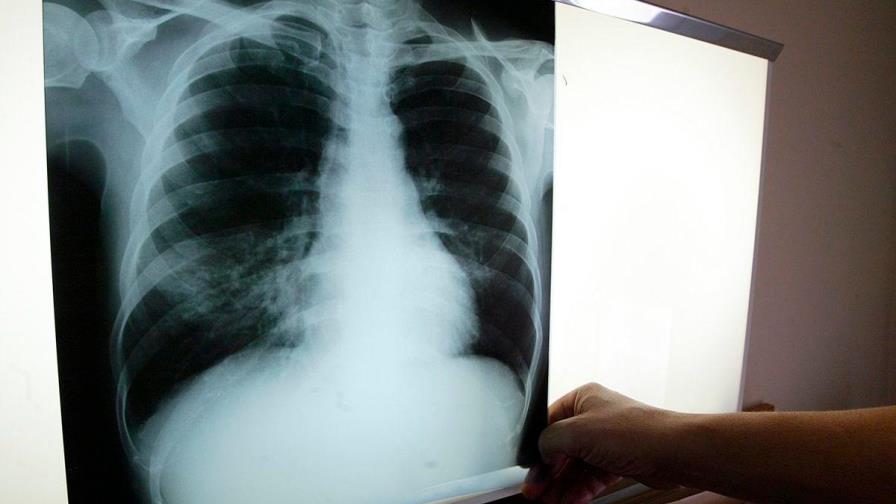

La organización humanitaria Médicos Sin Fronteras (MSF) anunció hoy que ha desarrollado un tratamiento contra la tuberculosis resistente que es más fácil de administrar, más corto y causa menos efectos secundarios que los que produce la combinación de fármacos que se utilizan actualmente.

El nuevo régimen es totalmente oral, tiene seis meses de duración y está dirigido a tratar a enfermos que han desarrollado una tuberculosis resistente a la rifampicina, que es el tratamiento generalizado.

El estándar de atención actual puede tardar hasta 20 meses en completarse, requiere inyecciones dolorosas y la ingesta de hasta 20 píldoras diarias que pueden provocar efectos secundarios muy graves, todo lo cual al final solo cura a uno de cada dos enfermos.